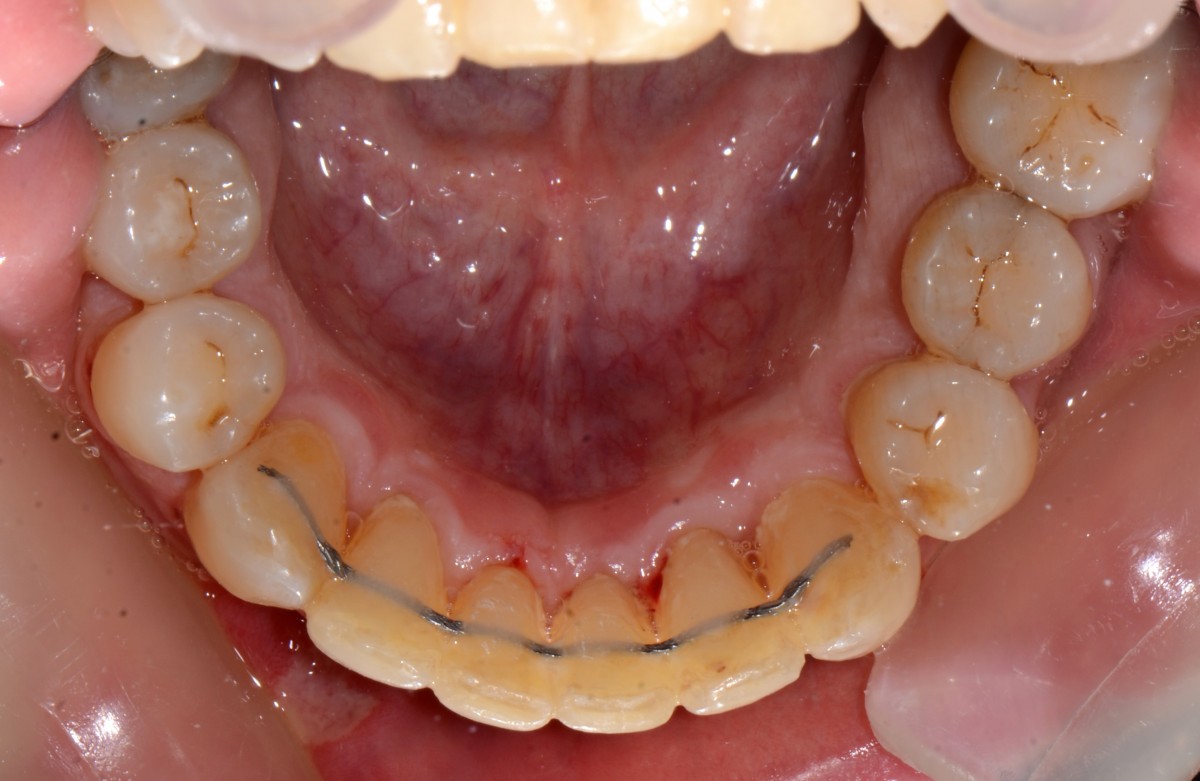

G.L., 51 years old patient, pre- sented to the clinic with Class I malocclusion, deep bite with complete coverage of lower in- cisors, big median diastema between teeth #11 and #21, lack of interdental papilla and poor oral hygiene (figs. 3, 4).

Lower incisors erupted verti- cally and created 2 planes of occlusion and exaggerated curve of spee in the lower arch. The upper lip “pushed” the an- terior incisors lingually and consequently the bite was deepened. Oral hygiene is poor mainly due to the crowding of the lower incisors. The upper diastema resulted in the loss of the interdental papilla between the central incisors (figs. 5, 6).

Patient had gone through pre- vious orthodontic treatment

with extraction of upper first premolars (#14, #24). Space between #11-#21 is slowly opened during the years and space start to develop distally to the upper lateral incisors. Lower incisors are hitting traumatically the palate creat- ing proliferation of the epithe- lium and constant inflamma- tion. Lower anterior crowding is around 4.5 mm (#33-#43) (figs. 7, 8).